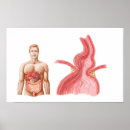

Medical Ilustration Of A Hiatal Hernia In The Poster

PriceCA$50.75